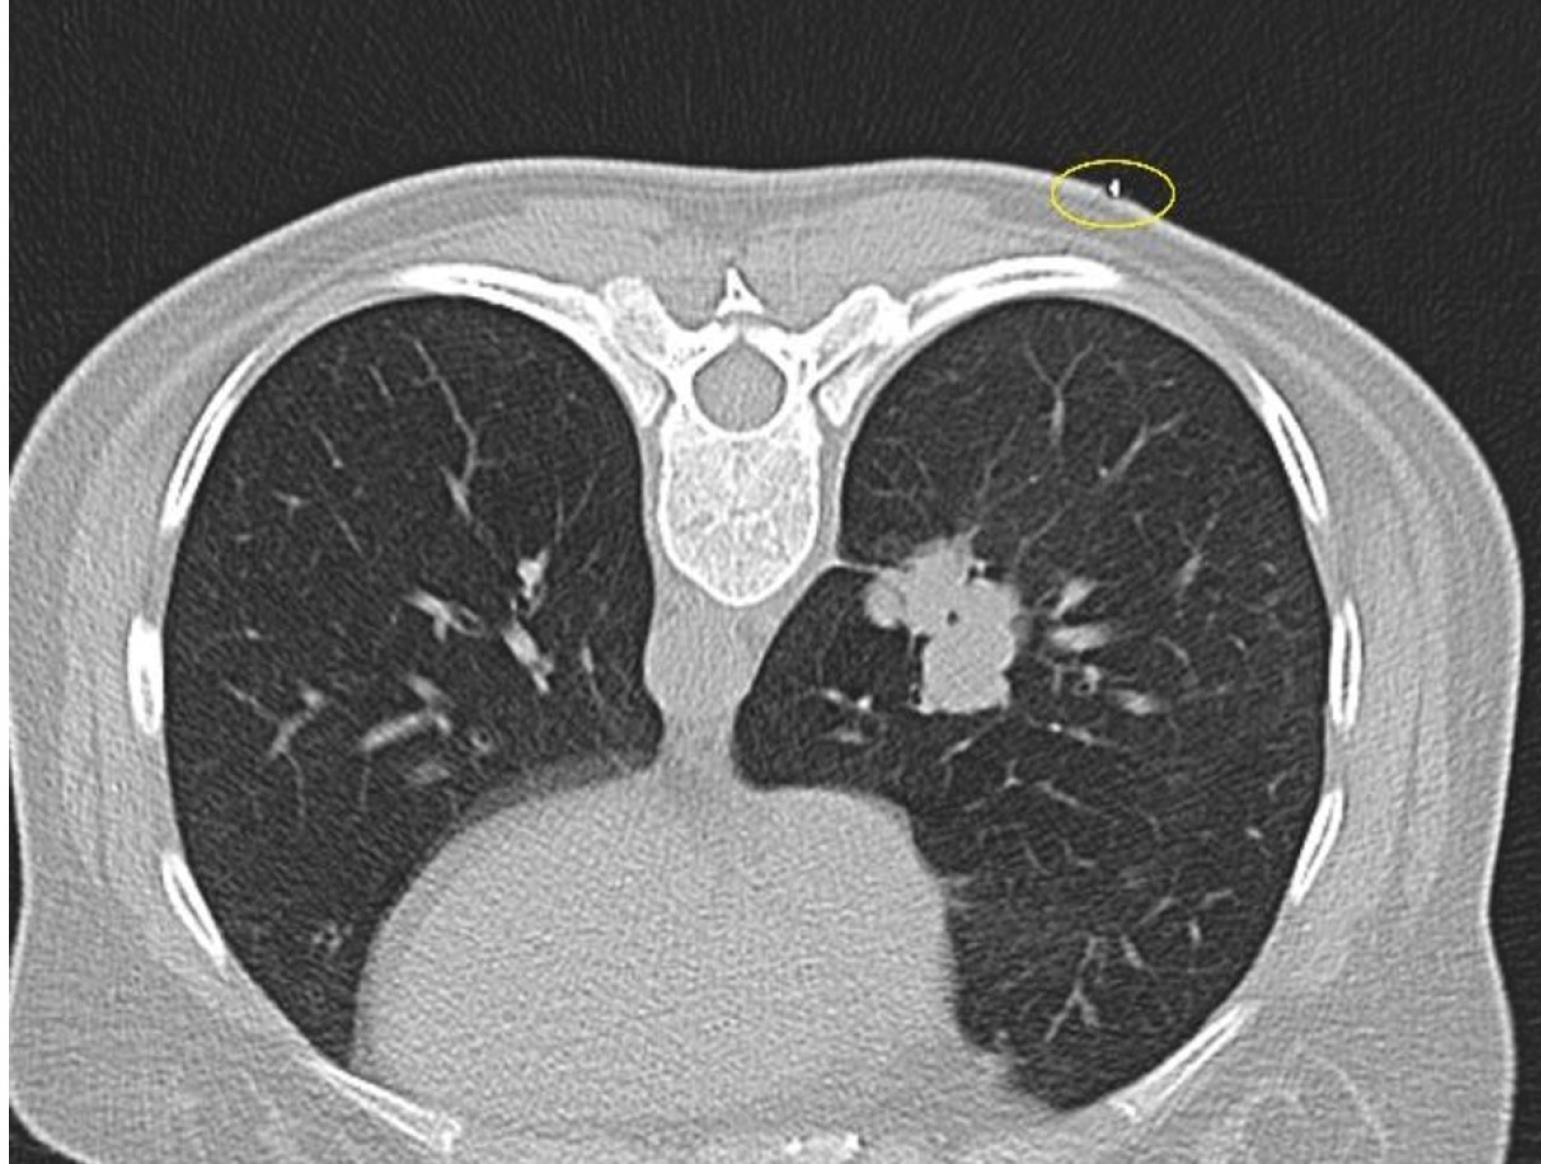

The patient’s hospitalization position was determined as supine, prone, or lateral decubitus by evaluating the previous CT images and planning the entry distance from the closest location to the lesion. If a lesion is on the anterior, the supine position; if it is on the posterior, the prone position, and if it is located close to the lateral thoracic wall, the lateral decubitus position is selected. By looking at the previous CT images of the patient, the patient was hospitalized in the most appropriate place planned for the intervention. Then, an axial CT scanogram scan including the lesion was performed. After that, a metallic marker (closed injector tip) was placed on the skin and the image was retaken (Figure 1).

Figure 1.

The marker is used for localization on the skin (yellow circle) in the right lung mass lesion CT from the most suitable prone position